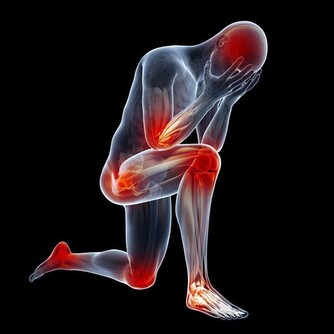

血管堵塞的症狀

1、 胸口悶痛

中老年人身上如果出現了胸口疼痛的現象,有可能是由於血管堵塞導致的。因為血管堵塞會導致人的身上出現心臟供血不足的現象,進而就會導致人的身上出現胸口疼痛的現象。

2、 四肢腫脹疼痛

四肢肢是人體供血的最末端,當血管堵塞後,四肢的供血和回血不足就會出現腫脹現象。四肢組織處於缺血缺氧狀態下就會伴隨有疼痛的表現,特別是靜脈血栓發生後,腫脹症狀更為明顯。

3、 頭痛

腦部血管堵塞會出現間歇性的劇烈頭痛,但持續時間並不會很長,大約只有幾秒鐘的時間,然後痛感會逐漸消失。這正是大腦組織短暫缺血的症狀,如果一周之內頻頻發生的話,就需要警惕腦梗疾病發作!

4、 流鼻血

人的血管出現堵塞的話,會導致患者體內的血壓升高,進而導致人的身上出現流鼻血的現象,這對人的身體健康產生的不良影響也是很大的,所以說如果人身上出現了經常流鼻血的現象,大家一定要加以重視。

5、 皮膚淤青

人的血管出現堵塞,會導致人身上的血液循環出現問題,進而就會導致人的身上出現血栓,而血栓則會導致人的身上出現皮膚淤青,這對人的外貌產生的不良影響很大。

血管堵塞很危險,特別是中老年人群。小堵容易誘發中風,高血壓等疾病,而嚴重的堵塞會直接導致腦血栓、腦梗塞或直接猝死。所以在平時,清理血管很重要!